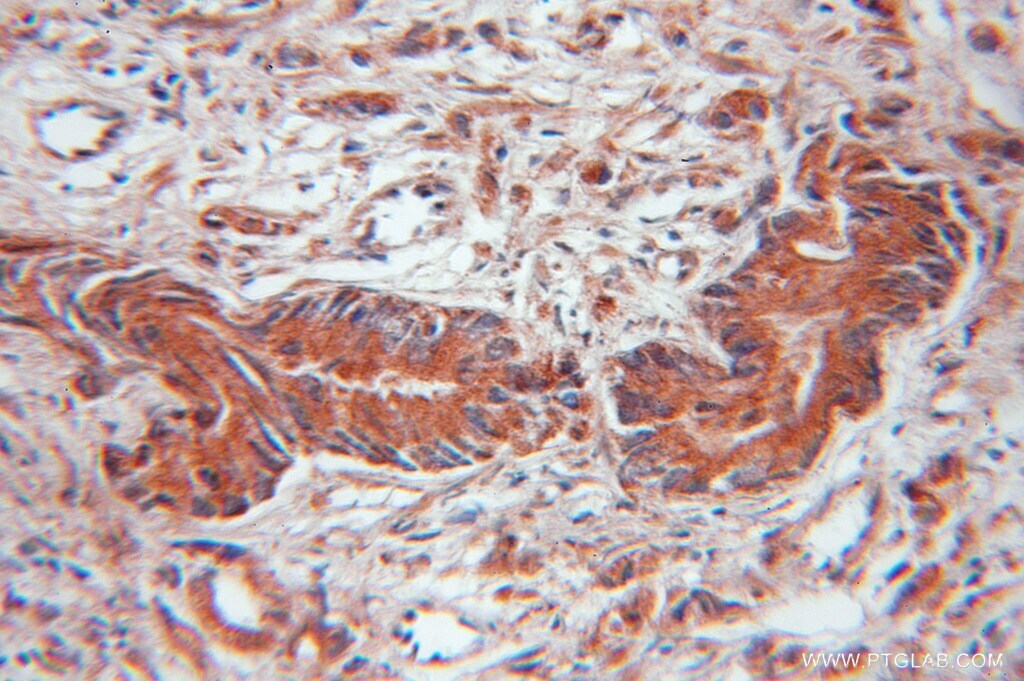

Supportive validation

- Submitted by

- Invitrogen Antibodies (provider)

- Main image

- Experimental details

- Immunohistochemistry of paraffin-embedded human prostate cancer using 11182-1-AP (EIF4EBP2 antibody) at dilution of 1:100 (under 10x lens).